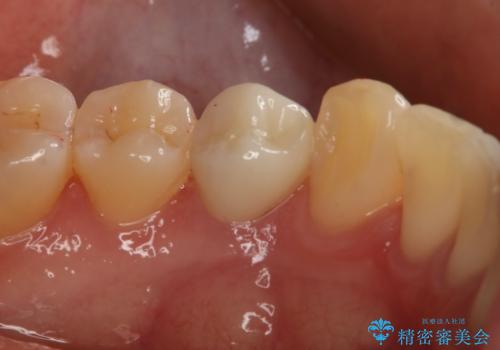

- 左下4番のう蝕を指摘され治療を希望された患者様です。

切削量などを考慮しクラウンでの治療を提案したところ、セラミックを希望されたのでフルジルコニアクラウンでの治療を選択しました。

- 99000円(フルジルコニアクラウン+仮歯)費用は治療当時の料金となります

う蝕が深かったので痛みが出る可能性をお伝えしましたが特に症状は現れなかったので、予定通りセラミッククラウンでの治療を行いました。